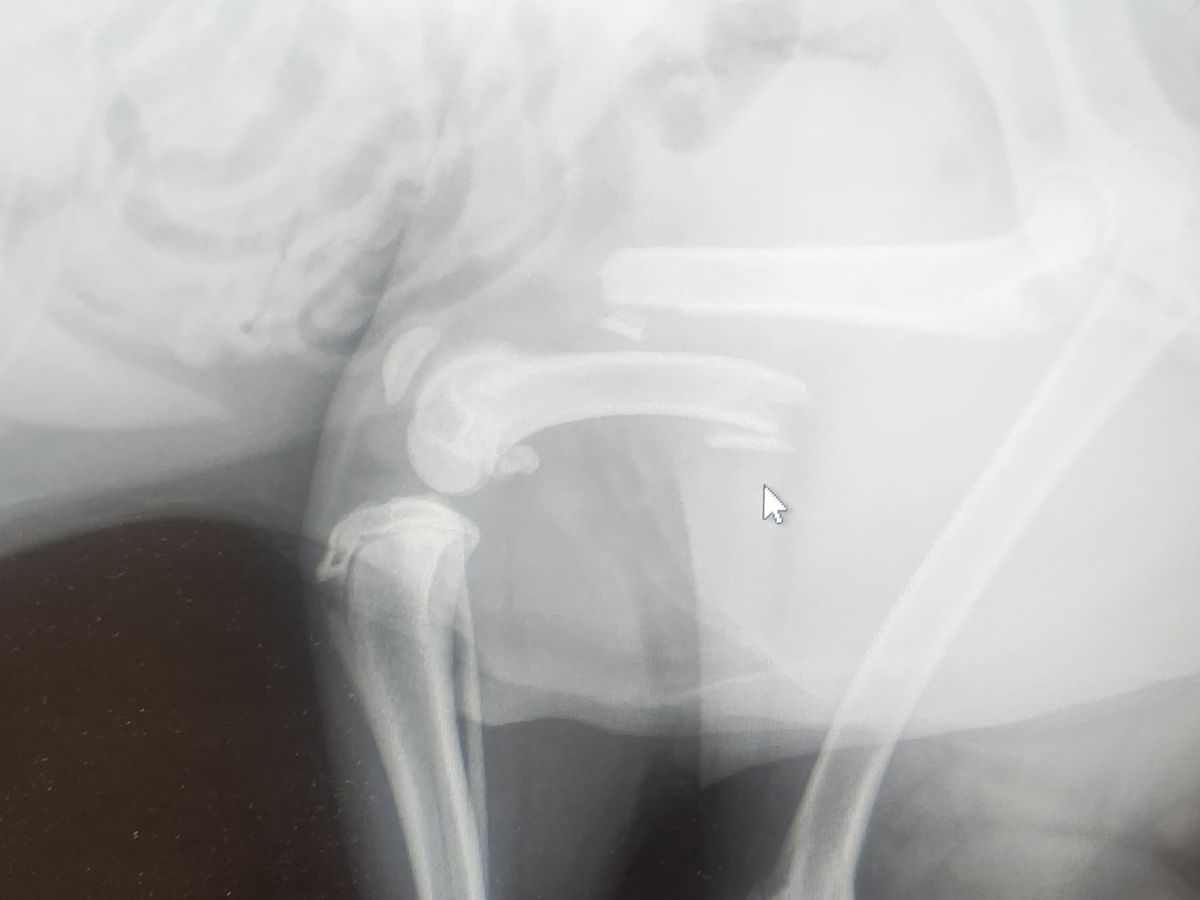

Hi, my names Tyrell and I'm starting this fundraiser for my blue heeler Winston, the poor pup jumped/fell out the car window while on a car ride with my family member, there definitely could have been precautions to avoid it and there will be in the future, but right now he didn't get by with a just a few scrapes, he has a break in the femur bone. Although I do have income I am currently broke and having to scrounge up random debts that I can obtain while also paying the bills, the surgery could be thousands of dollars and is already staring to cost more then I make per pay check, if you could donate anything we'd be very blessed and grateful, and they have confirmed the femur to be fully broken and just amputation could cost up to $2500. Due to the vet not having overnight stay he is currently back with us on heavy paid med and sedatives with a still broken leg, time is of the essence while the vet gets quotes from difference orthopedic surgeons and we scrounge up the money to pay for it, amputation is not our desired outcome but we are already struggling with the amputation cost. Any donations will go towards helping VCA Northpointe Animal Hospital try and save his leg first so he can continue to be our 4 legged hyper dog.